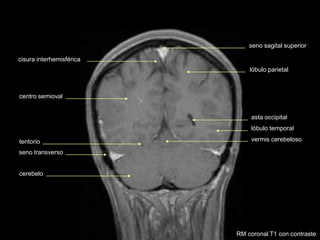

seno sagital superior

cisura interhemisférica

centro semioval

tentorio

cerebelo

lóbulo parietal

lóbulo temporal

seno transverso

vermis cerebeloso

RM coronal T1 con contraste